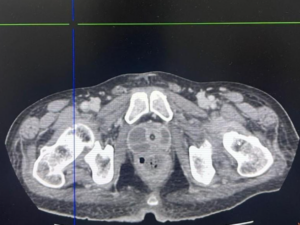

Paciente de 52 anos, sem comorbidades prévias, procura a emergência por apresentar há 4 dias febre e disúria e há 24 horas complicou com intensa dor pélvica e dificuldade para urinária.

Tomografia computadorizada de abdome tem o seguinte achado:

Qual diagnóstico?

DProstatite aguda complicada com abscesso prostático